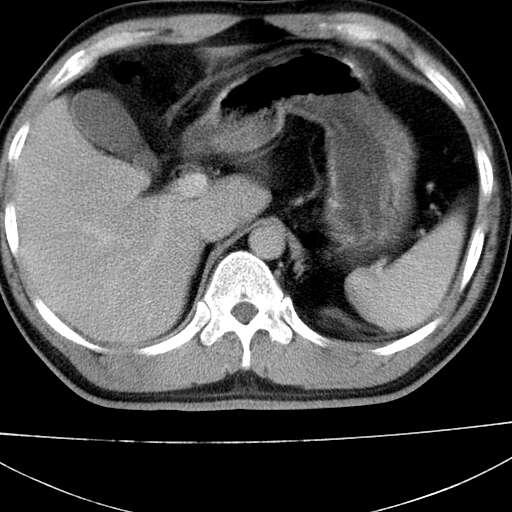

标题: CT21921:腹膜后腔肿物。患者男39Y。体检。增强扫描时间欠准

左侧膈肌脚外缘见一结节样软组织影,密度较均匀,与胸膜关系稍密切,增强轻度强化;考虑来自胸膜良性病变(胸膜纤维瘤可能)。建议加扫胸部ct检查。

2、左下膈肌脚外缘结节状病变,与胸膜交界面呈锐角,胸膜下脂肪线可见,定位于肺内,考虑支气管囊肿或肺隔离征可能性大。

膈疝

左肋隔角占位,考虑胸膜间皮瘤

1)考虑左肺下叶后基底段(或左下胸后壁胸膜)软组织团块,性质待定;建议行进一步检查。2)左肾结石。

左膈肌连续性中断,左侧膈疝可能性大.

左膈肌角后腹膜腔见肿物影,其内见脂肪密度灶及软组织密度灶,强化不明显。病灶大部在后腹膜内。考虑异位嗜铬细胞瘤或脂肪肉瘤、畸胎瘤

考虑左肺下叶后基底段肺隔离症?胸膜间皮瘤?